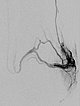

In der digitalen Subtraktionsangiographie, der Katheter liegt in der linken Arteria glutea superior, finden sich multiple, kaum identifizierbare kleine arteriovenöse Fisteln wie sie für die diffusen arteriovenösen Malformationen beim Parkes-Weber-Syndrom typisch sind.

Superselektive digitale Subtraktionsangiographie über einen Mikrokatheter in der Arteria glutea superior in einem distalen Ast. Der Nidus der feinfistulösen arteriovenösen Malformation zeigt so feine Shunts, dass diese anatomisch in der Angiographie kaum aufgelöst werden können.

Während der Embolisation über den Mikrokatheter (nicht abgebildet) in Roadmap-Technik wird das Embolisat (Ethylen-Vinyl-Alkohol-Kopolymer) in den Nidus bis in den venösen Abstrom der AVM vorgedrückt um auch die kleinesten Fisteln zu verschließen („plug & push“-Technik).